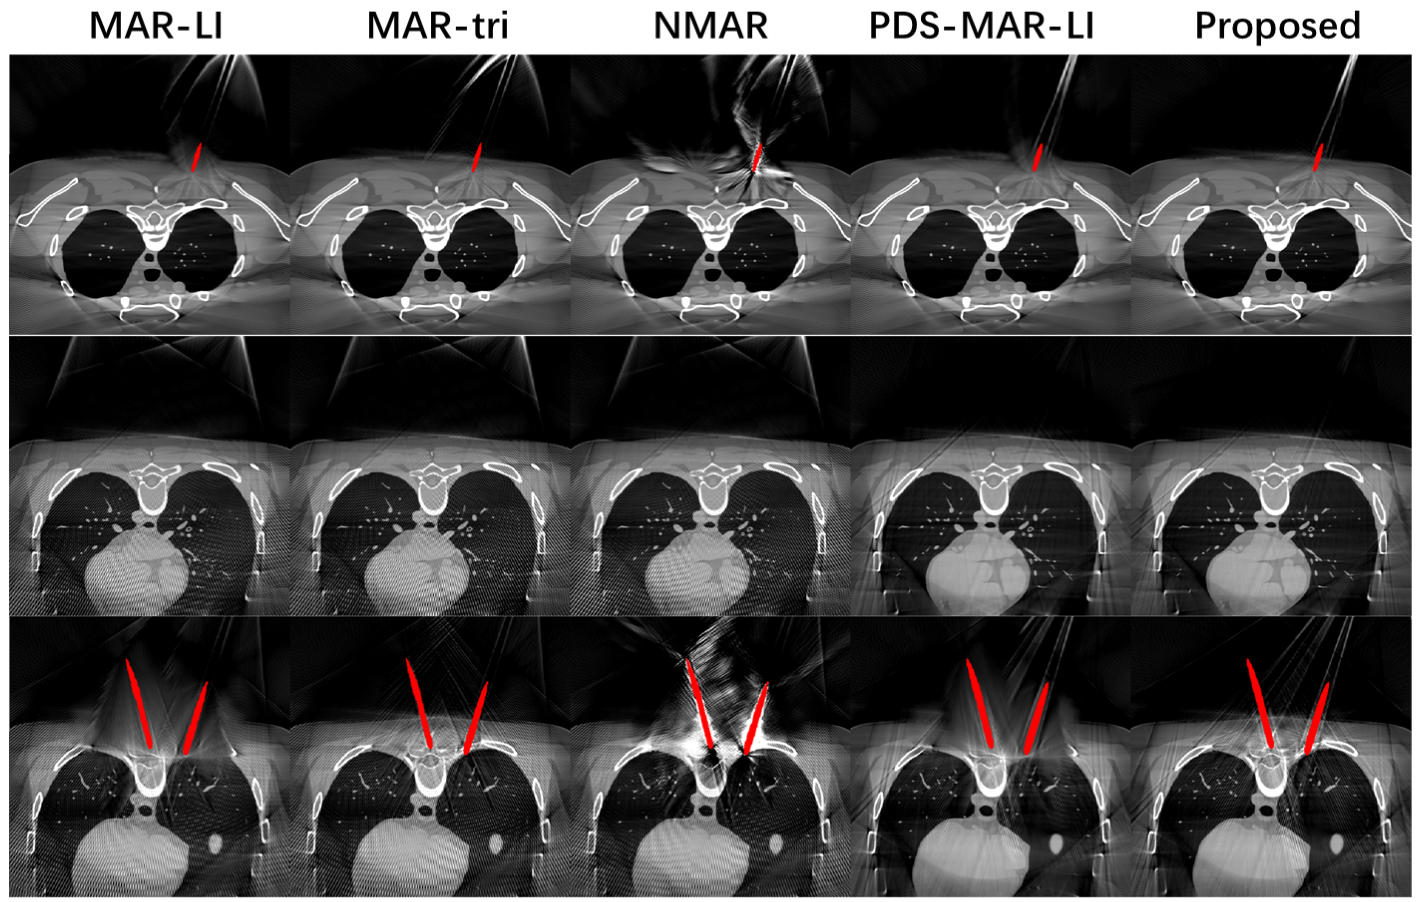

Fig. 4 gives a visual comparison between the reconstruction results of different algorithms. Generally, image domain segmentation-based methods (MAR-LI, MAR-tri and NMAR) suffer from severe streak artifacts resulting from metal objects out of scanning FoV. Linear interpolation-based algorithms (MAR-LI, PDS-MAR-LI) suffer from over-smoothing near metal objects, and tissue contrast details get lost. The proposed algorithm shows much-reduced streak artifacts and sharper tissue boundaries around metal implants than other algorithms. However, the proposed algorithm does not eliminate streak artifacts totally, since there are still interpolation failures in the projection domain (orange arrows in Fig. 3).

Fig. 6 provides the reconstructed results from sheep body data. Unlike in digital phantom data, results on animal body data suffer from severe segmentation failures in the image domain with a threshold. Some K-wires are partially segmented (the left one in Fig. 6 (a1-a4)) some are not found at all (the left one in Fig. 6 (b1-b4), the one in Fig. 6 (c1-c4)). The missegmentation in the image domain causes a significant metal trace missing in the projection domain which further leads to uncorrected metal artifacts in the reconstructed images. Generally, the proposed algorithm reconstructs image slices with substantially reduced metal artifacts and tissue details that are preserved. In addition, the proposed metal mask reconstruction method is able to preserve the correct image domain metal mask even when the thresholding strategy fails.

The reconstruction results for the abdominal phantom are depicted in Fig. 8. Similar to the animal body results, conventional image domain segmentation suffers from segmentation faults and results in incomplete metal artifact suppression (see Fig. 8 (c2-c3)) and secondary artifacts (see Fig. 8 (a3)). The proposed algorithm shows superior ability in metal artifact reduction, and the metal masks are well-reconstructed with our multiplicative-form backprojection method. Furthermore, streak artifacts introduced by metal objects outside FoV are still observed even on slices without metal in Fov for image domain segmentation methods (bottom of Fig. 8 (b2-b3)) while being totally eliminated by the proposed method (Fig. 8 (b5)).